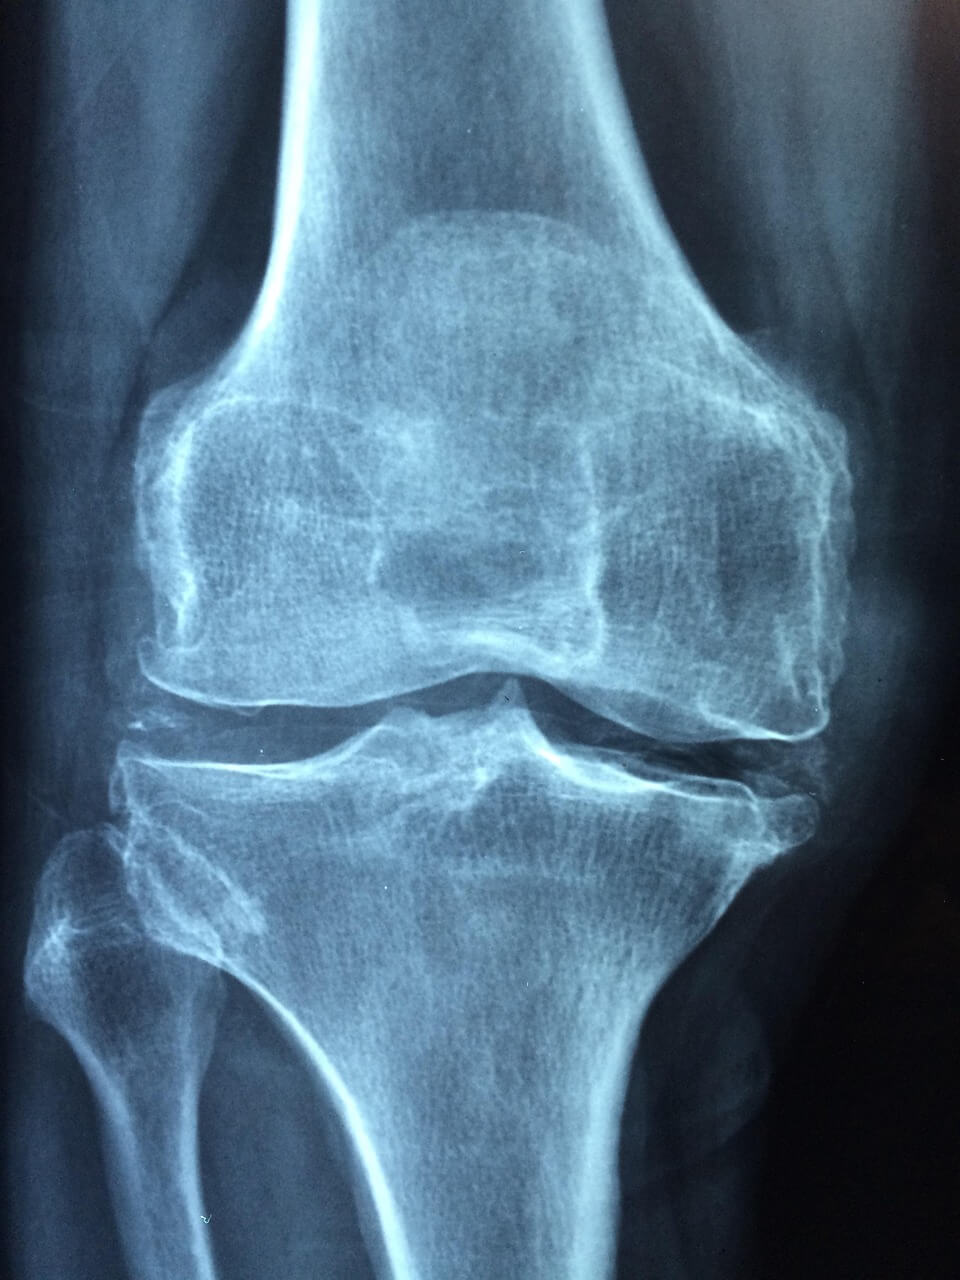

- 퇴행성 관절염

50대 이후 가장 흔한 무릎 통증의 원인은 퇴행성 관절염입니다. 연골이 닳아 없어지며 뼈끼리 맞닿아 통증과 변형이 발생합니다.

증상/관리

- 아침에 뻣뻣함

- 걷기 불편, O자 다리

체중 감량, 운동, 약물치료, 주사치료가 일반적이며, 심한 경우 인공관절 치환술이 필요합니다.

7. 무릎 통증 진단 방법

- 이학적 검사 – 관절 움직임과 안정성 확인

- 영상 검사 – X-ray, MRI, 초음파

- 정기 검진: 40대 이후에는 정기적으로 X-ray, MRI 검사를 통해 조기 진단을 권장합니다.